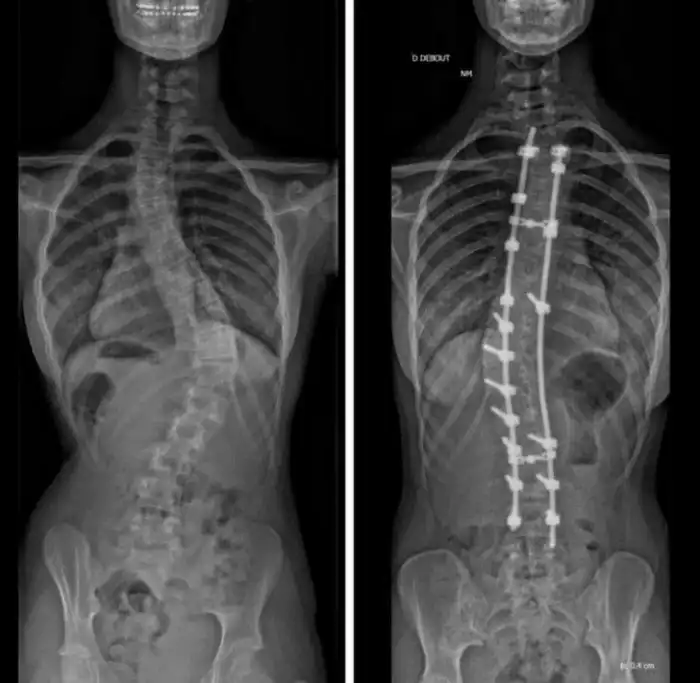

«6 лет назад мне провели операцию по выпрямлению позвоночника. После этого я стала на 5 см выше»